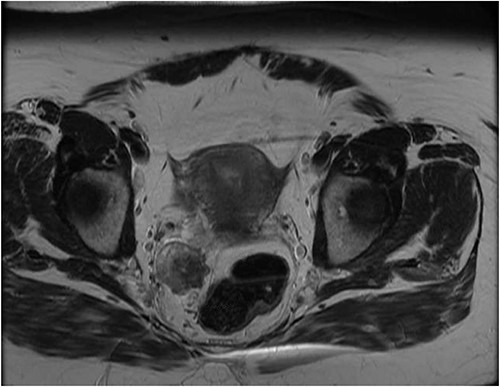

Her physical exam was normal. A right extraluminal mass was barely palpable on digital rectal examination. The pararectal mass showed no hypermetabolic activity on recent positron emission tomography (PET) scan. Either a GIST or a NET was suspected. Gallium-68 Dotatate PET scan revealed high expression of somatostatin receptors (Fig. 2). Pelvic magnetic resonance imaging (MRI) showed an isodense lesion, slightly heterogenous, on T1-weighted images with persistent T2 hyperintensity and restricted diffusion (Fig. 3). It was infiltrating the right lateral mesorectum without direct contact with the rectal wall. Colonoscopy showed no endoluminal lesion. Two ultrasound-guided fine needle aspirations (EUS-FNA) were unconclusive and patient developed osteodiscitis. Transgluteal CT-guided biopsy finally revealed the presence of thyroid tissue. Listed diagnoses were teratoma, tailgut cyst, or less likely, thyroid carcinoma. Subsequent thyroid ultrasonography revealed four non-specific micronodules. Thyroid function tests were normal, except for primary hyperparathyroidism. Parathyroid sestamibi scan suggested a single adenoma. A multidisciplinary team was made up of colorectal, head and neck, and orthopedic surgeons, along with an endocrinologist. The case was discussed at the Colorectal Tumor Board. A collaborative two-step surgical approach was proposed.

Latest pelvic MRI on initial consultation (T2-weighted images).